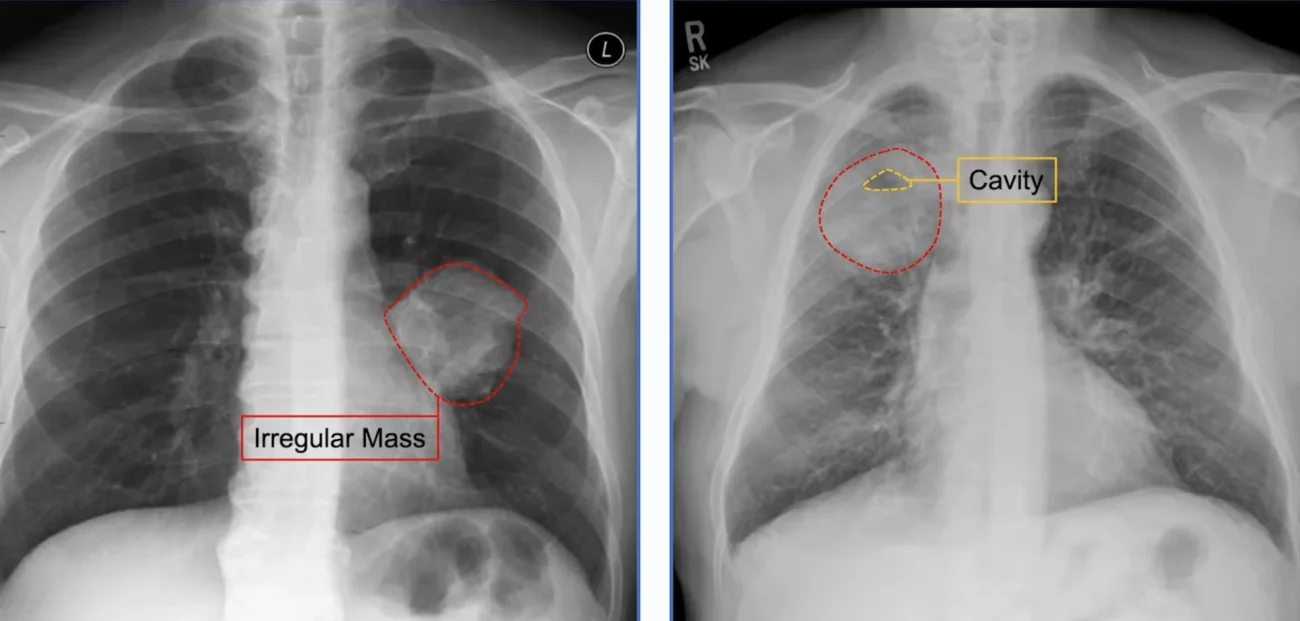

Cavitation Inside Pneumonia: A Sign That Should Not Be Ignored

Some types of pneumonia can form a cavity inside the consolidated area of the lung. On an X-ray, this appears as a white patch (the consolidation) with a dark area inside it — sometimes with a visible fluid level, indicating the cavity contains both liquid and air. This is called a cavitating pneumonia or lung abscess.

Cavitation in pneumonia almost always suggests a more serious or aggressive infection. A lung abscess is when a necrotic (dying) area within the pneumonia forms a pocket of pus that becomes walled off. It looks like a round, thick-walled cavity on X-ray, often with an air-fluid level. The treatment is prolonged antibiotic therapy, and sometimes drainage or surgery is needed.